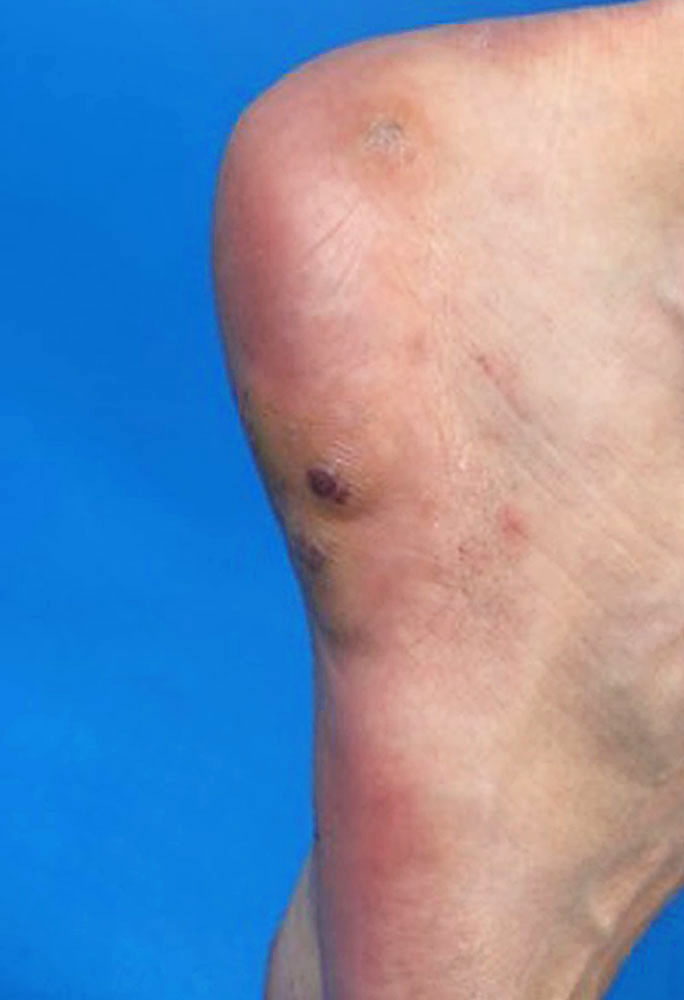

Maffucci syndrome is characterized by multiple enchondromas, often visible as circumscribed dermal distensions of fingers and/or toes in combination with spindle cell hemangiomas. Synonym: enchondromatosis Ollier-Maffucci.

The overgrowth in Maffucci syndrome is characterized by hard, yellowish, indolent skin protuberances (enchondromas) attributable to a bone and originating from dysplastic cartilage tissue. These can be unilateral or bilateral, but are usually clearly asymmetric. Depending on their location, enchondromas can cause growth reduction and curvature of affected limb segments. The forearms and lower legs are most commonly affected, but hands and feet are often affected as well.

The vascular changes in Maffucci syndrome are multifocal, dermal, bluish-reddish vascular nodules of the hypodermis (“spindle cell hemangiomas”) that are similar to, but histologically distinct from, a venous malformation.